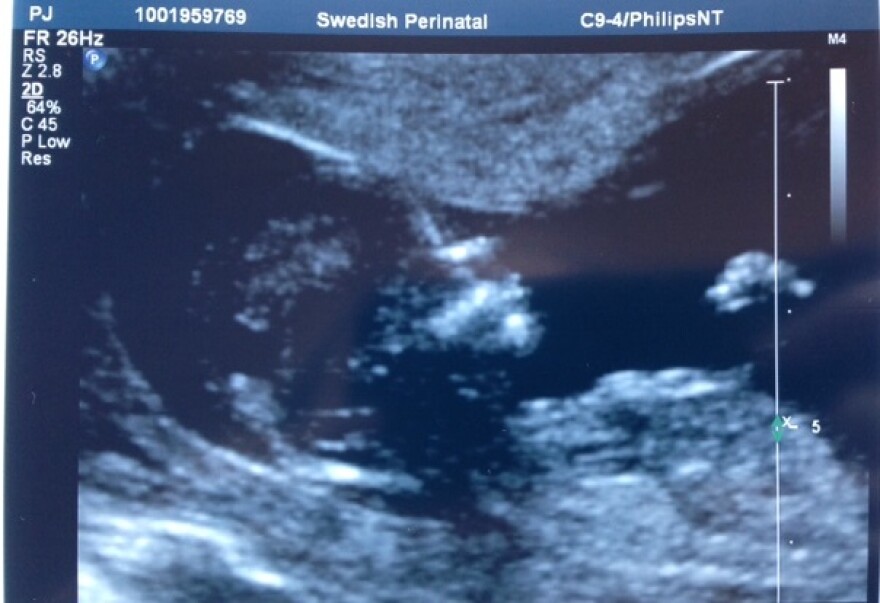

UW research links ultrasound to severity of some autism

Ultrasound should not be done on pregnant women in their first trimester unless medically necessary.

A University of Washington researcher says a new autism study reinforces that federal recommendation.